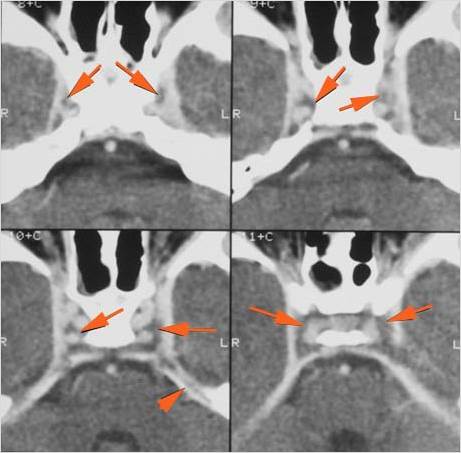

Orbits

The extraconal orbital fat is abnormal. [Yes/No]

There is a subperiosteal abscess or edema along the medial wall, roof or floor of the orbit. [Yes/No]

The extraocular muscles are swollen or otherwise abnormal. [Yes/No]

There is bone erosion along the walls of the orbit. [Yes/No]

The intraconal orbital fat is infiltrated. [Yes/No]

The orbital apex and the superior and inferior orbital fissures are infiltrated. [Yes/No]

The superior and/or inferior ophthalmic veins are dilated or thrombosed. [Yes/No]

There is evidence of thrombus, thrombophlebitis or other occlusive or inflammatory process of the cavernous sinus. [Yes/No]

There is evidence of inflammation of the distal internal carotid artery. [Yes/No]